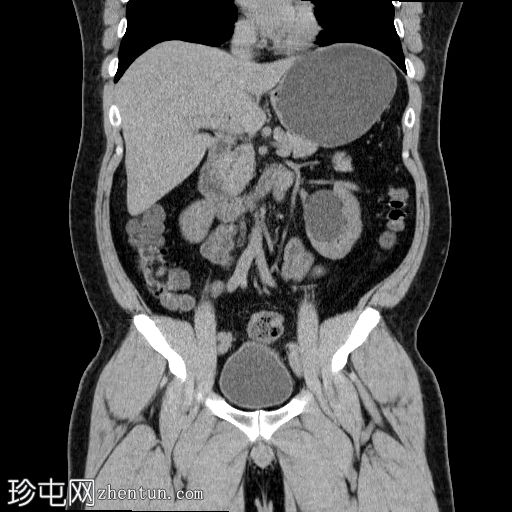

冠状位

平扫

左侧肾盂输尿管连接部(PUJ)可见一枚较大的不透射线结石,最大直径达24 mm,平均CT值约为1160 HU。该结石引起反压改变,导致明显的左肾积水。

此外,左肾中极肾盏内可见一枚直径约13 mm的非梗阻性不透射线结石,平均CT值为1100 HU。

另外,左肾下极肾盏内可见多枚聚集性不透射线结石,总直径约20 mm,平均CT值约为1140 HU。

偶然发现的异常包括前列腺内多发粗大钙化灶,主要位于尿道周围,并伴有轻度肝肿大。

输尿管肾盂交界处(PUJ)梗阻是肾积水的常见原因,可以是先天性的,也可以是后天性的。在成人中,最常见的原因是梗阻性结石,正如本病例所示。

密度值(>1100 HU)提示草酸钙或混合钙结石,这类结石通常质地较硬,体外冲击波碎石术(ESWL)难以将其击碎,因此通常需要其他介入治疗,例如输尿管镜检查、经皮肾镜取石术或手术治疗。